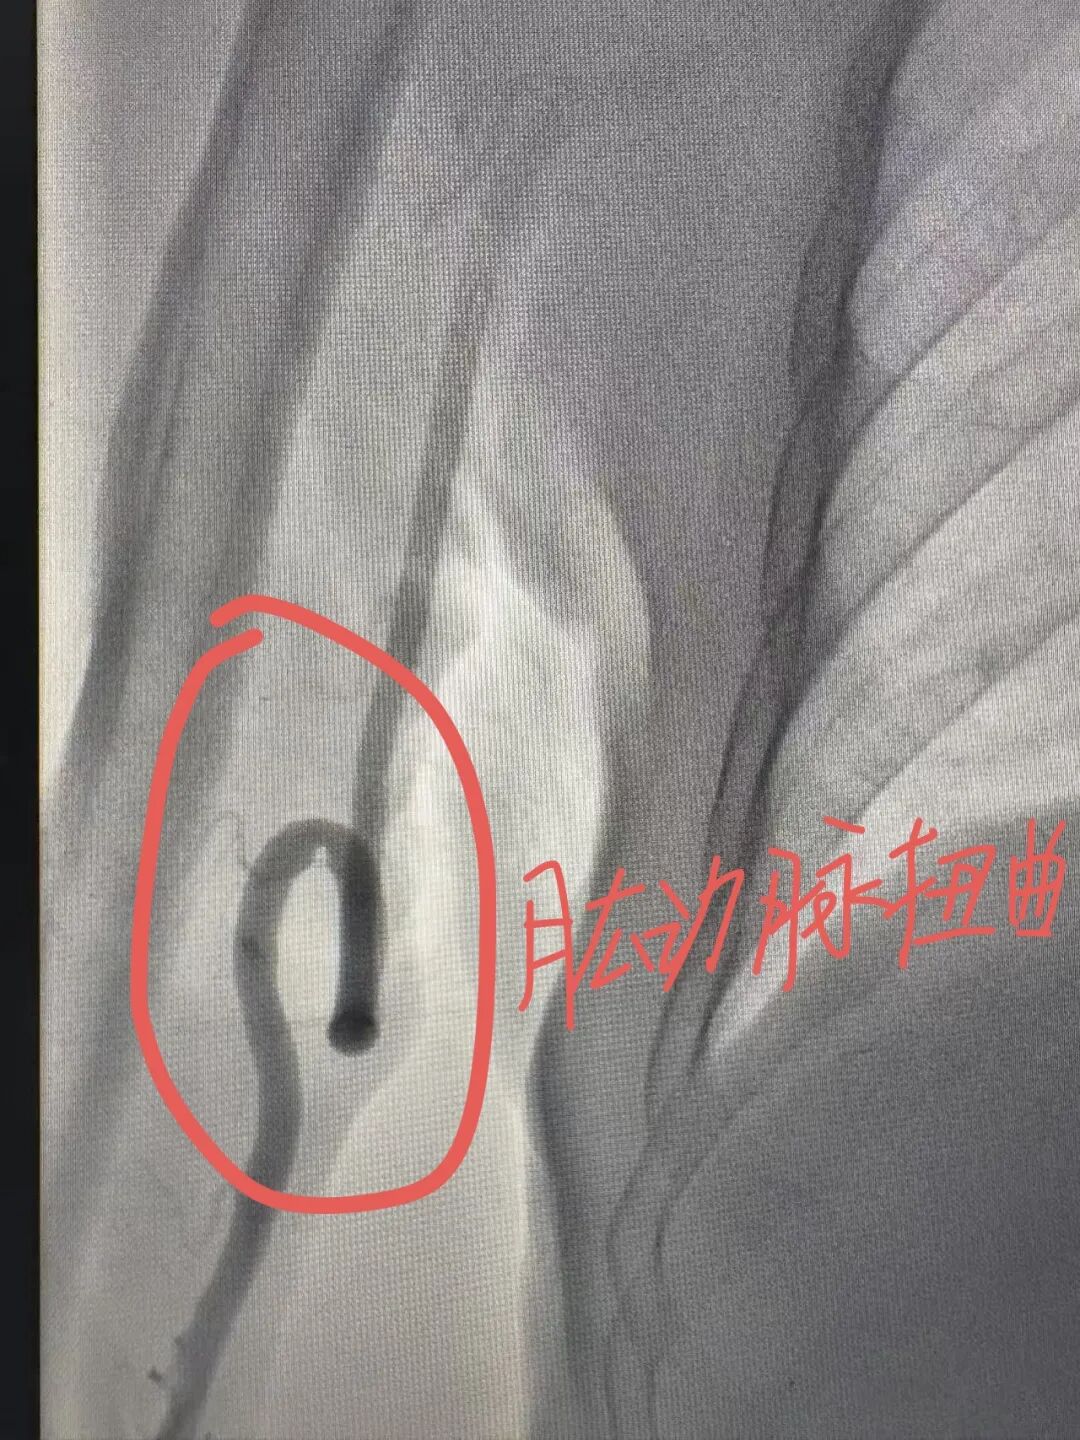

介入术中发现,在常规右侧桡动脉入路时,发现患者的桡动脉、肱动脉、锁骨下动脉血管严重扭曲,仿佛是一条蜿蜒曲折、布满荆棘的山路,导丝难以通过,手术一度受阻。关键时刻,介入团队冷静应对,主治医师罗科伟凭借娴熟技术与对血管结构的精确把握,耐心调整导丝方向,最终顺利将其送至主动脉根部,成功完成造影。